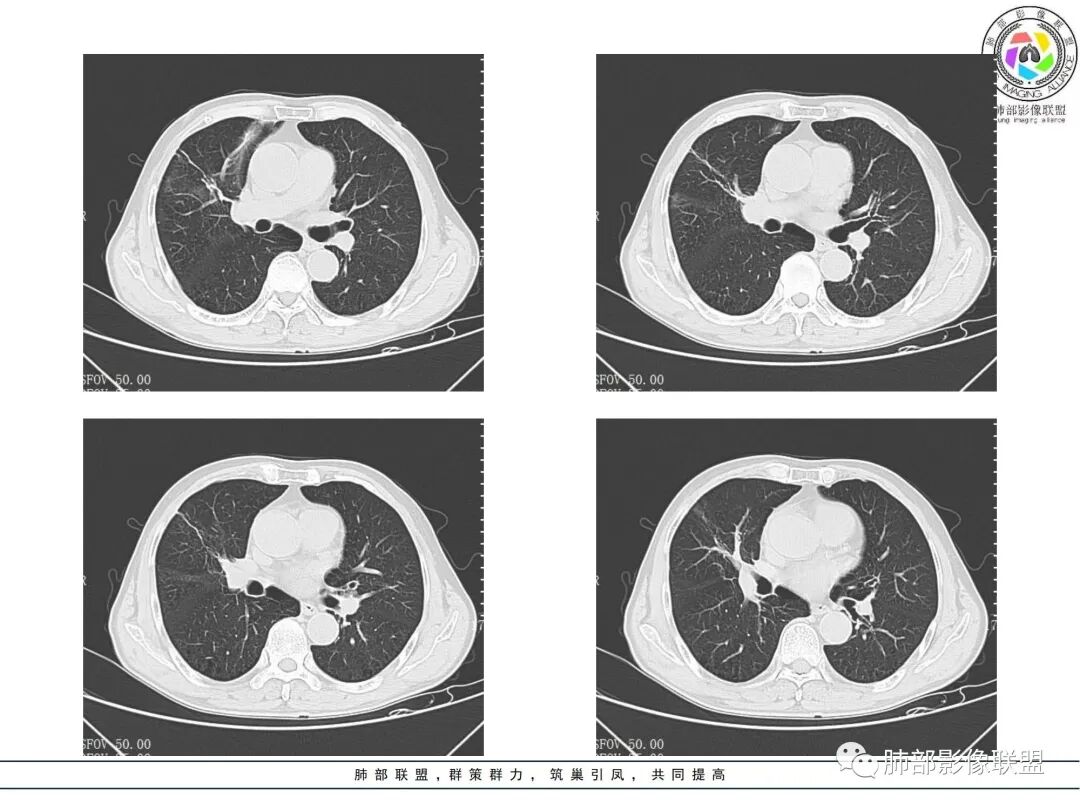

晨读病例,老年男性,乏力,纳差,近来发热,右肺上叶团片状阴影,内见空洞,空洞内壁不光滑,见短液平,增强病灶壁可见不均匀强化,似有边界不清晰的坏死,病灶周围可见片状模糊阴影,考虑恶性病变,鳞癌或腺癌伴感染。

老年男性,肺气肿背景,右肺较大分叶状肿块,密度不均,内坏死空洞形成,坏死区边界不规则,周围多发斑片蜂窝状、网格状高密度影,考虑鳞癌合并感染

右肺上叶及中叶不规则肿块伴周围模糊影,其内小叶间质结节样改变,肿块不均匀强化,坏死及空洞,坏死边界不清,血管显示尚可,考虑腺癌,鉴别淋巴瘤

老年男性,有咳嗽发热。右肺中上叶团状软组织肿块,周围磨玻璃渗出改变,病灶内密度不均,可见低密度坏死及空洞影,空洞内壁凹凸不平,近肺门侧可见明显大面积坏死。近端支气管堵塞不明显。考虑恶性肿瘤伴感染,腺癌?鉴别鳞癌,感染性病变。

右肺上叶团片状阴影,内见空洞,空洞内壁不光滑,偏心,,增强不均匀强化,内有边界不清晰的坏死,病灶周围可见片状模糊阴影,右下肺也有磨玻璃病灶,Crp高,腺癌

70岁男性,发烧病史,右肺巨大肿块,边缘分叶,内部空洞,洞内见附壁结节,局部支气管阻塞,肿块周围见大片阻塞性炎症;实验室检查,炎性指标增高;考虑恶性肿瘤伴阻塞性肺炎,鳞癌可能。

老年男性,乏力,纳差,发热。右肺上叶团片状阴影,密度不均,可见低密度坏死,坏死边界不清,可见空洞形成,见短液平;增强病灶呈不均匀强化,其内血管边缘模糊毛糙;病灶周围可见斑片状渗出病灶,支气管未见明确阻塞。综上考虑肺癌伴感染,鳞癌可能。

老年男性,纳差和发热,炎症指标明显。右肺磨玻璃影伴有肿块,肿块呈膨胀性生长,内部没有气管影。首先考虑感染,并有肿瘤的表现。考虑鳞癌合并感染

右肺上叶实变,密度不均,内可见小气液平,周磨玻璃影,斜裂稍内凹,右下肺可见斑片影,强化可见血管走行自如,右侧胸腔少量积液,考虑感染性病变,努卡?放线菌?

老年男性,肺气肿背景,右肺上叶及中叶大范围实变影,边界不清,支气管通畅,其内见边缘膨隆软组织块影伴不规则坏死、空洞,增强扫描不均匀强化,洞壁显示不清,血管稍变细,实变影内另见多发囊样影,右肺下叶小片状影,病灶跨叶,炎性指标增高,感染应该有的,不除外合并恶性肿瘤(鳞癌?腺癌?)

男,70,反复乏力、纳差20天,发热1天。胸部CT:肺气肿背景,右肺上叶中叶大团片影,实变十磨玻璃渗出。增强实性斑片影内密度不均,可见多发低密度坏死及不规则空洞影,空洞内壁尚光滑,血管边缘模糊。支气管管壁增厚,管腔通畅。右下叶可见小片渗出影。考虑支气管肺炎进展?病原考虑能形成肉芽肿、坏死空洞的微生物,TB?奴卡?鉴别鳞癌。

老年男性,乏力纳差,进食量明显下降,发热,后期少许黄脓痰,无咯血。无胸痛。未提口腔卫生情况,发热时间段不明确,肺气肿背景,气管内痰拴还是其他?觉得是外朝内进展病灶,右肺多叶段病灶,支气管通畅,支气管壁弥漫增厚,实变病灶内有坏死,坏死边界比较清晰,血管破坏不明显,周围散在磨玻璃,边界模糊,无树芽,实变内可疑小钙化,右侧胸水,肺门纵隔淋巴结无明显肿大。病史不太支持化脓菌感染,真菌里隐球强化不太支持,结核需要排除,厌氧菌感染带排,冠状位矢状位病灶觉得类圆形,临床肿瘤也是不能轻易排除的